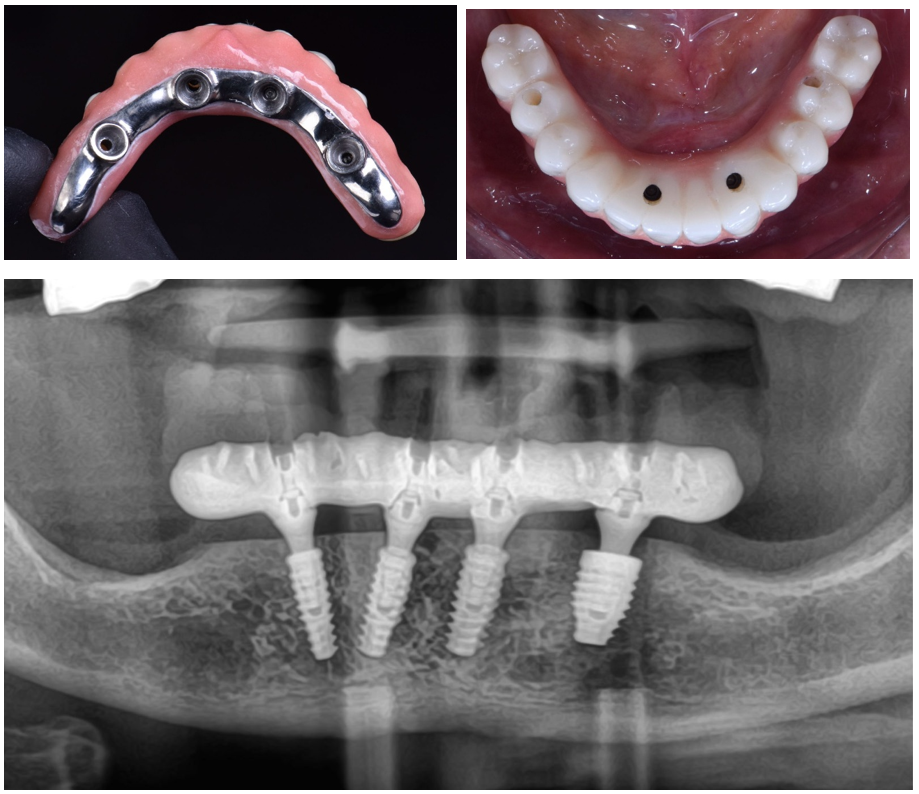

Com o escaneamento validado, demos sequência à confecção da prótese protocolo final.

A utilização do escaneamento intraoral na prática clínica torna os procedimentos mais rápidos e mais confortáveis para o paciente, eliminando as etapas de moldagem em um rebordo recém-operado. E os scan bodies de arco total Implacil Osstem facilitaram o escaneamento de arcos totais desdentados, garantindo precisão nos processos.